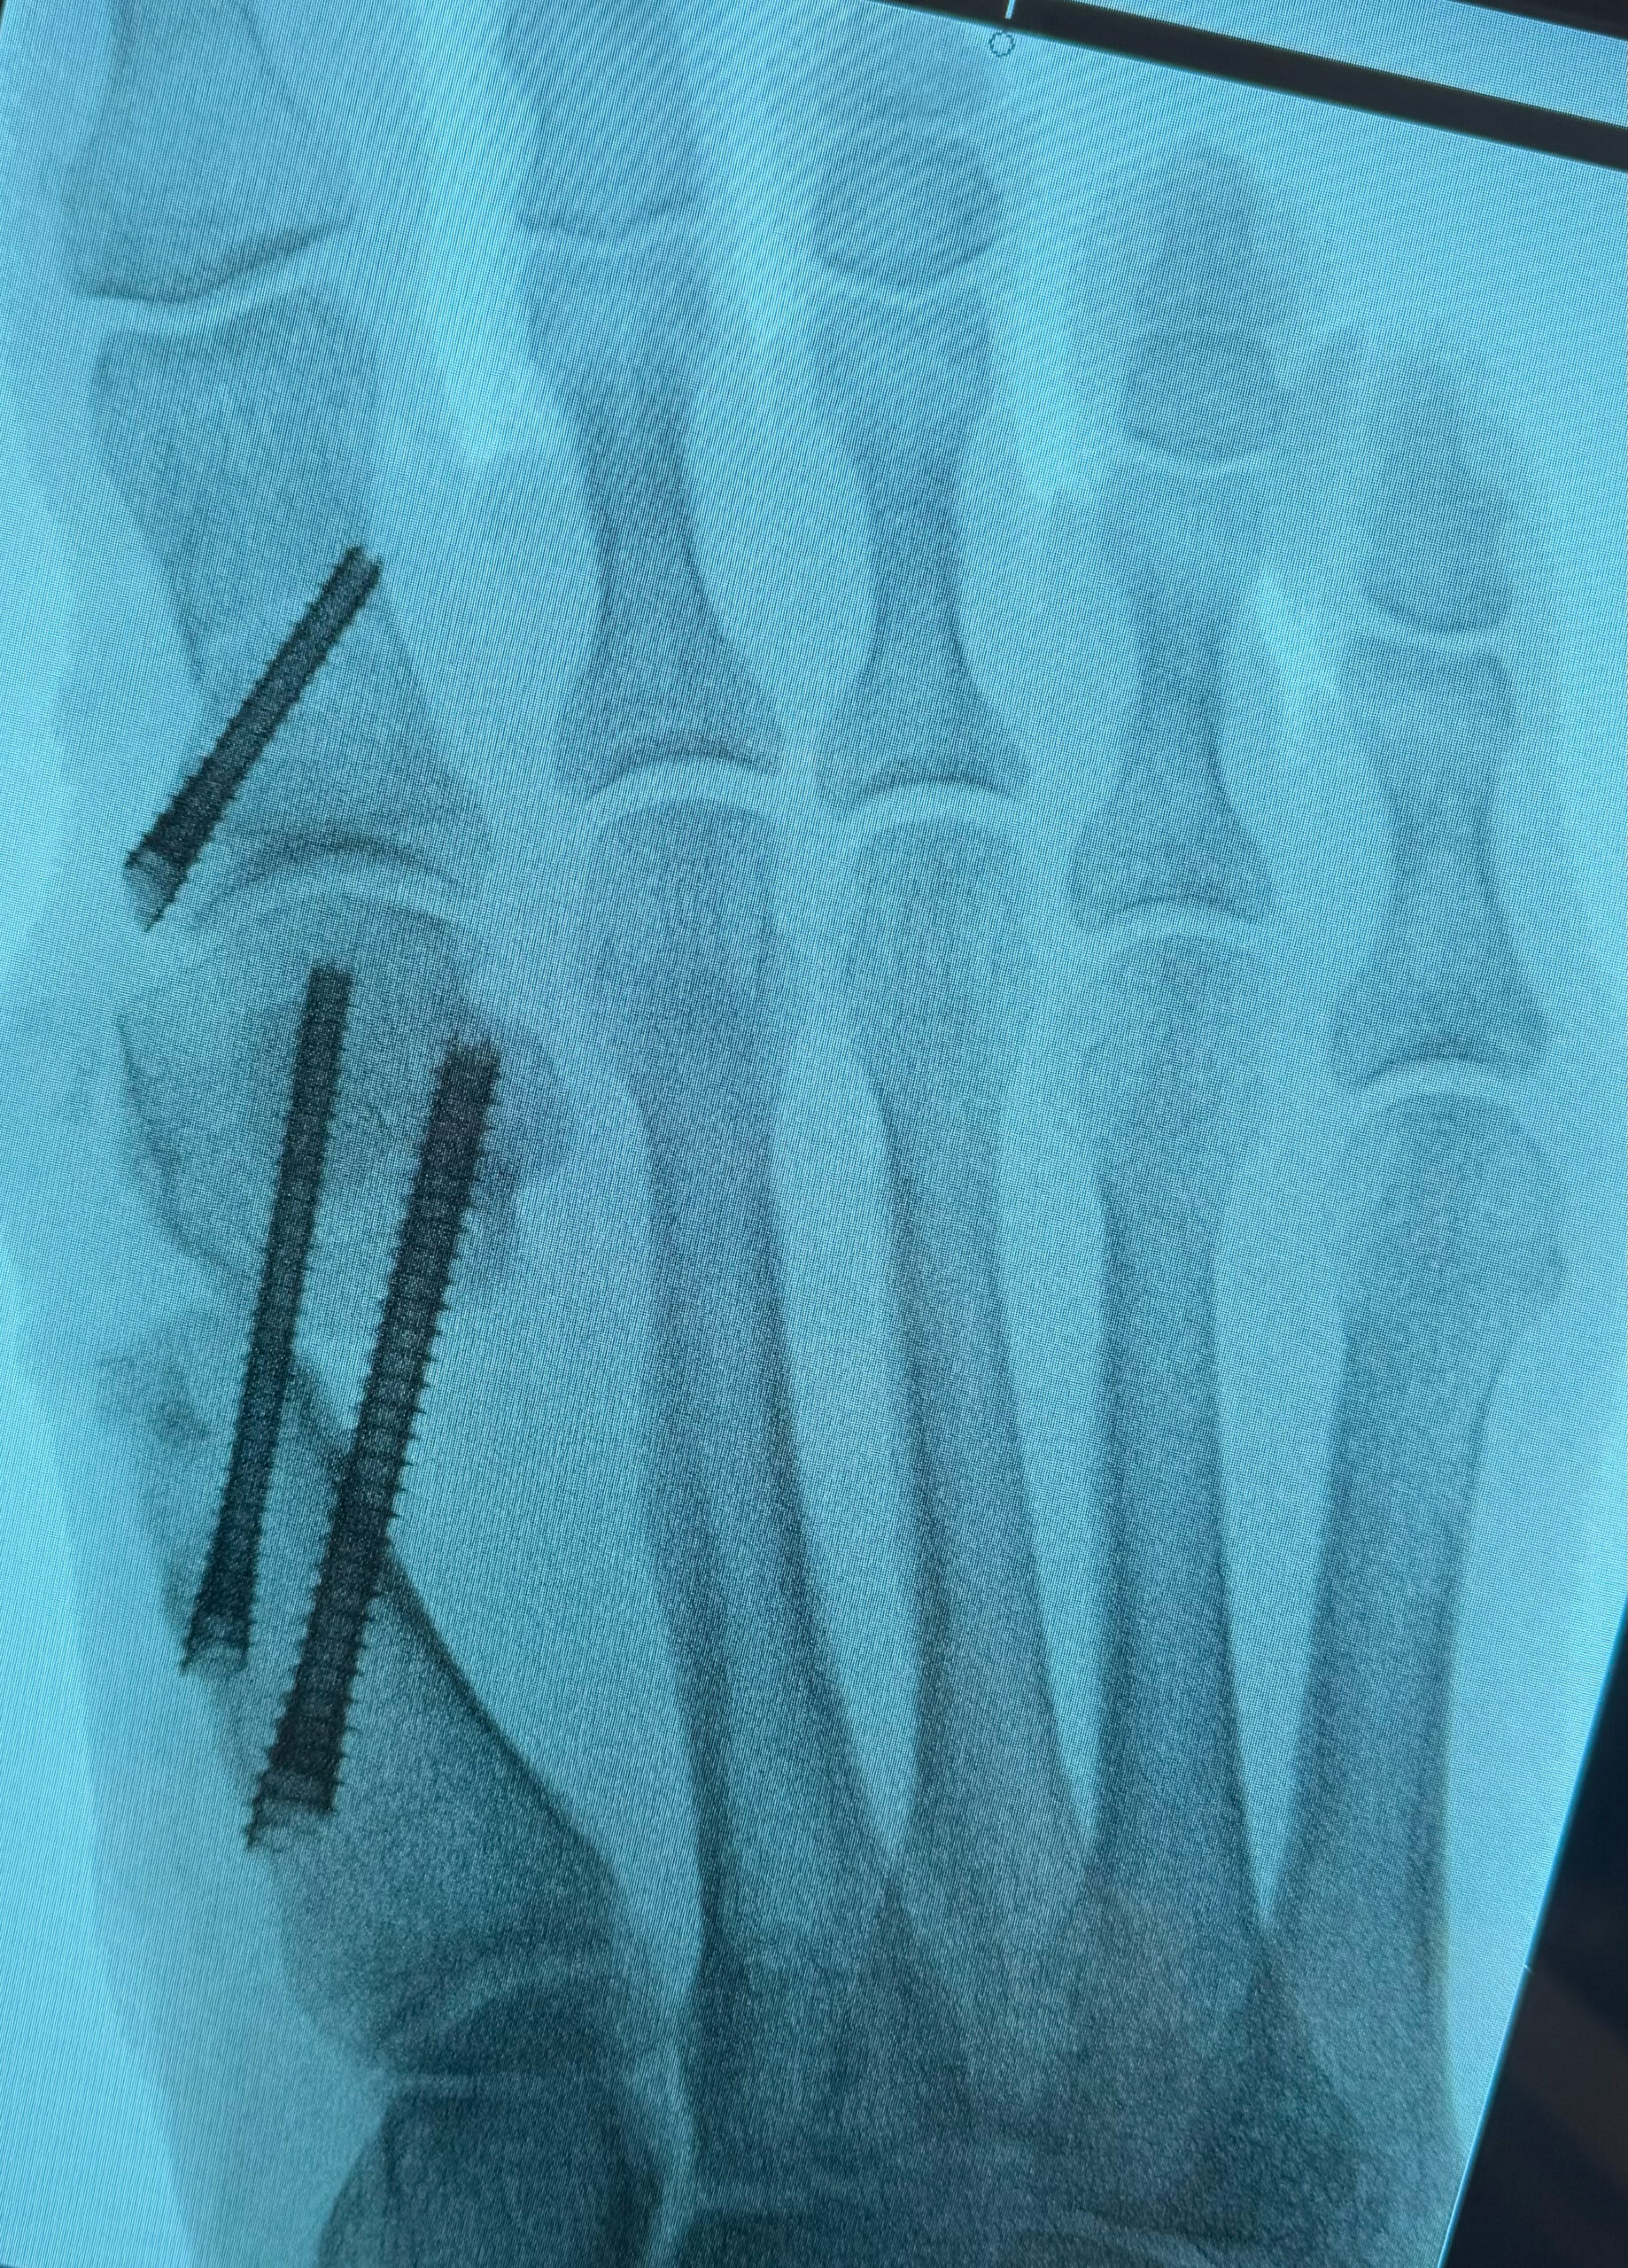

MIS Bunion

MIS3

MIS2